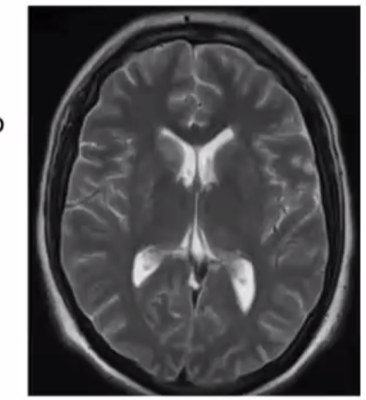

Qué se puede encontrar en la imagen

A

• Normal

• Hidrocefalia

• Criptococomas .> lesión ocupantes de espacio